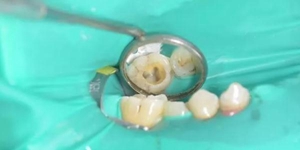

最近牙齦起膿包,總會有白色膿液流出,但不會痛,牙醫(yī)檢查出是根尖周炎,后面也做了排膿還消炎上藥,關(guān)鍵是做完根管治療膿包又長回來,奇怪的是,既然還會長膿包,那為什么要做根管治療?

說明根管治療中殘髓清除不徹底所致,實際上就是根管失敗了,正常的根管治療可以清理掉根尖內(nèi)病變的牙髓,根管消毒后把髓腔充填密封,但是牙膠尖不能超充,這樣你才不會再起膿包,不過根管前得先排膿再消炎上藥,一般感染物質(zhì)除去后,沒

有及時根管治療的話,瘺管口會自動關(guān)閉,感染性物質(zhì)還會卷土重來長出膿包。